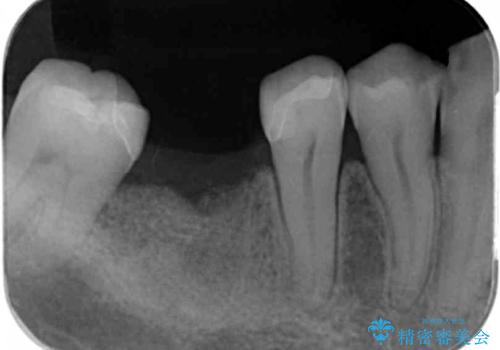

- 歯の破折により失ってしまった右下の歯の機能回復を求めて来院されました。

骨の増成を含むインプラント治療を計画します。

安定し、長く使用できるようなインプラント治療を実践するため、骨の増成をインプラント埋入と同時に行いました。